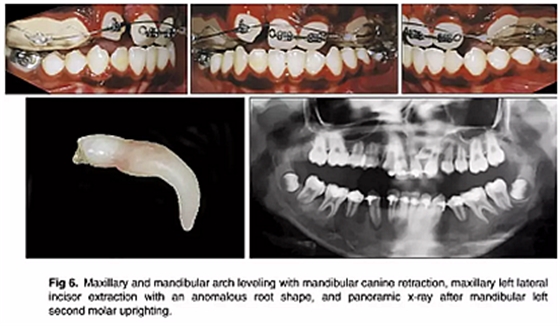

如全景片所示,下頜左側(cè)第二磨牙直立得以實(shí)現(xiàn)(圖6)。1年后,去除上頜擴(kuò)弓器,上下牙弓完全吻合。在上下牙弓中,用0.017×0.025英寸的鎳鈦弓絲進(jìn)行整平。上頜左側(cè)尖牙被移至側(cè)切牙位置; 下頜第一前磨牙被拔除,尖牙開始縮回。

隨后,由口腔頜面外科醫(yī)生(圖6 ; 圖7)拔除左右側(cè)側(cè)切牙,并使用直角弓來旋轉(zhuǎn)上頜磨牙并改善牙弓形態(tài); 在下頜弓中,尖牙的牽引繼續(xù)(圖7)。